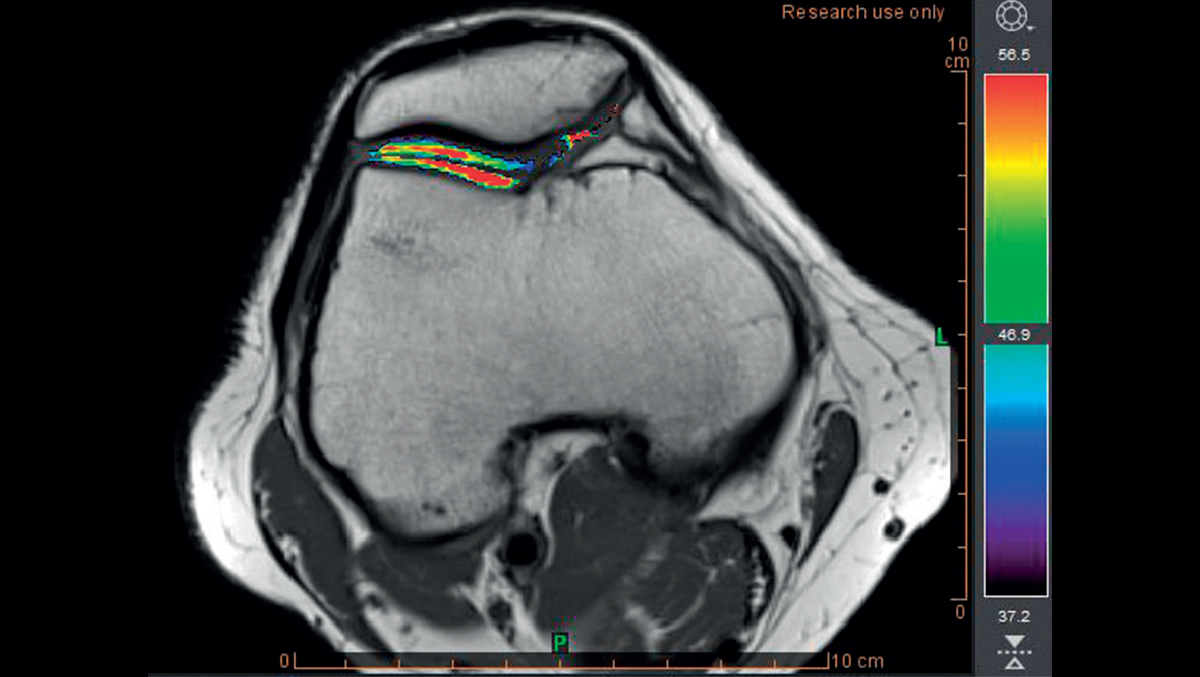

Опорно-двигательный аппарат

Диагностика и наблюдение за спортивными и ортопедическими заболеваниями

- Расчет отображения T2

- Раннее обнаружение разрушения хряща с помощью карты Thresholds T2

Обнаружение хрящевой ткани в группе риска с использованием пороговых значений времени релаксации T2